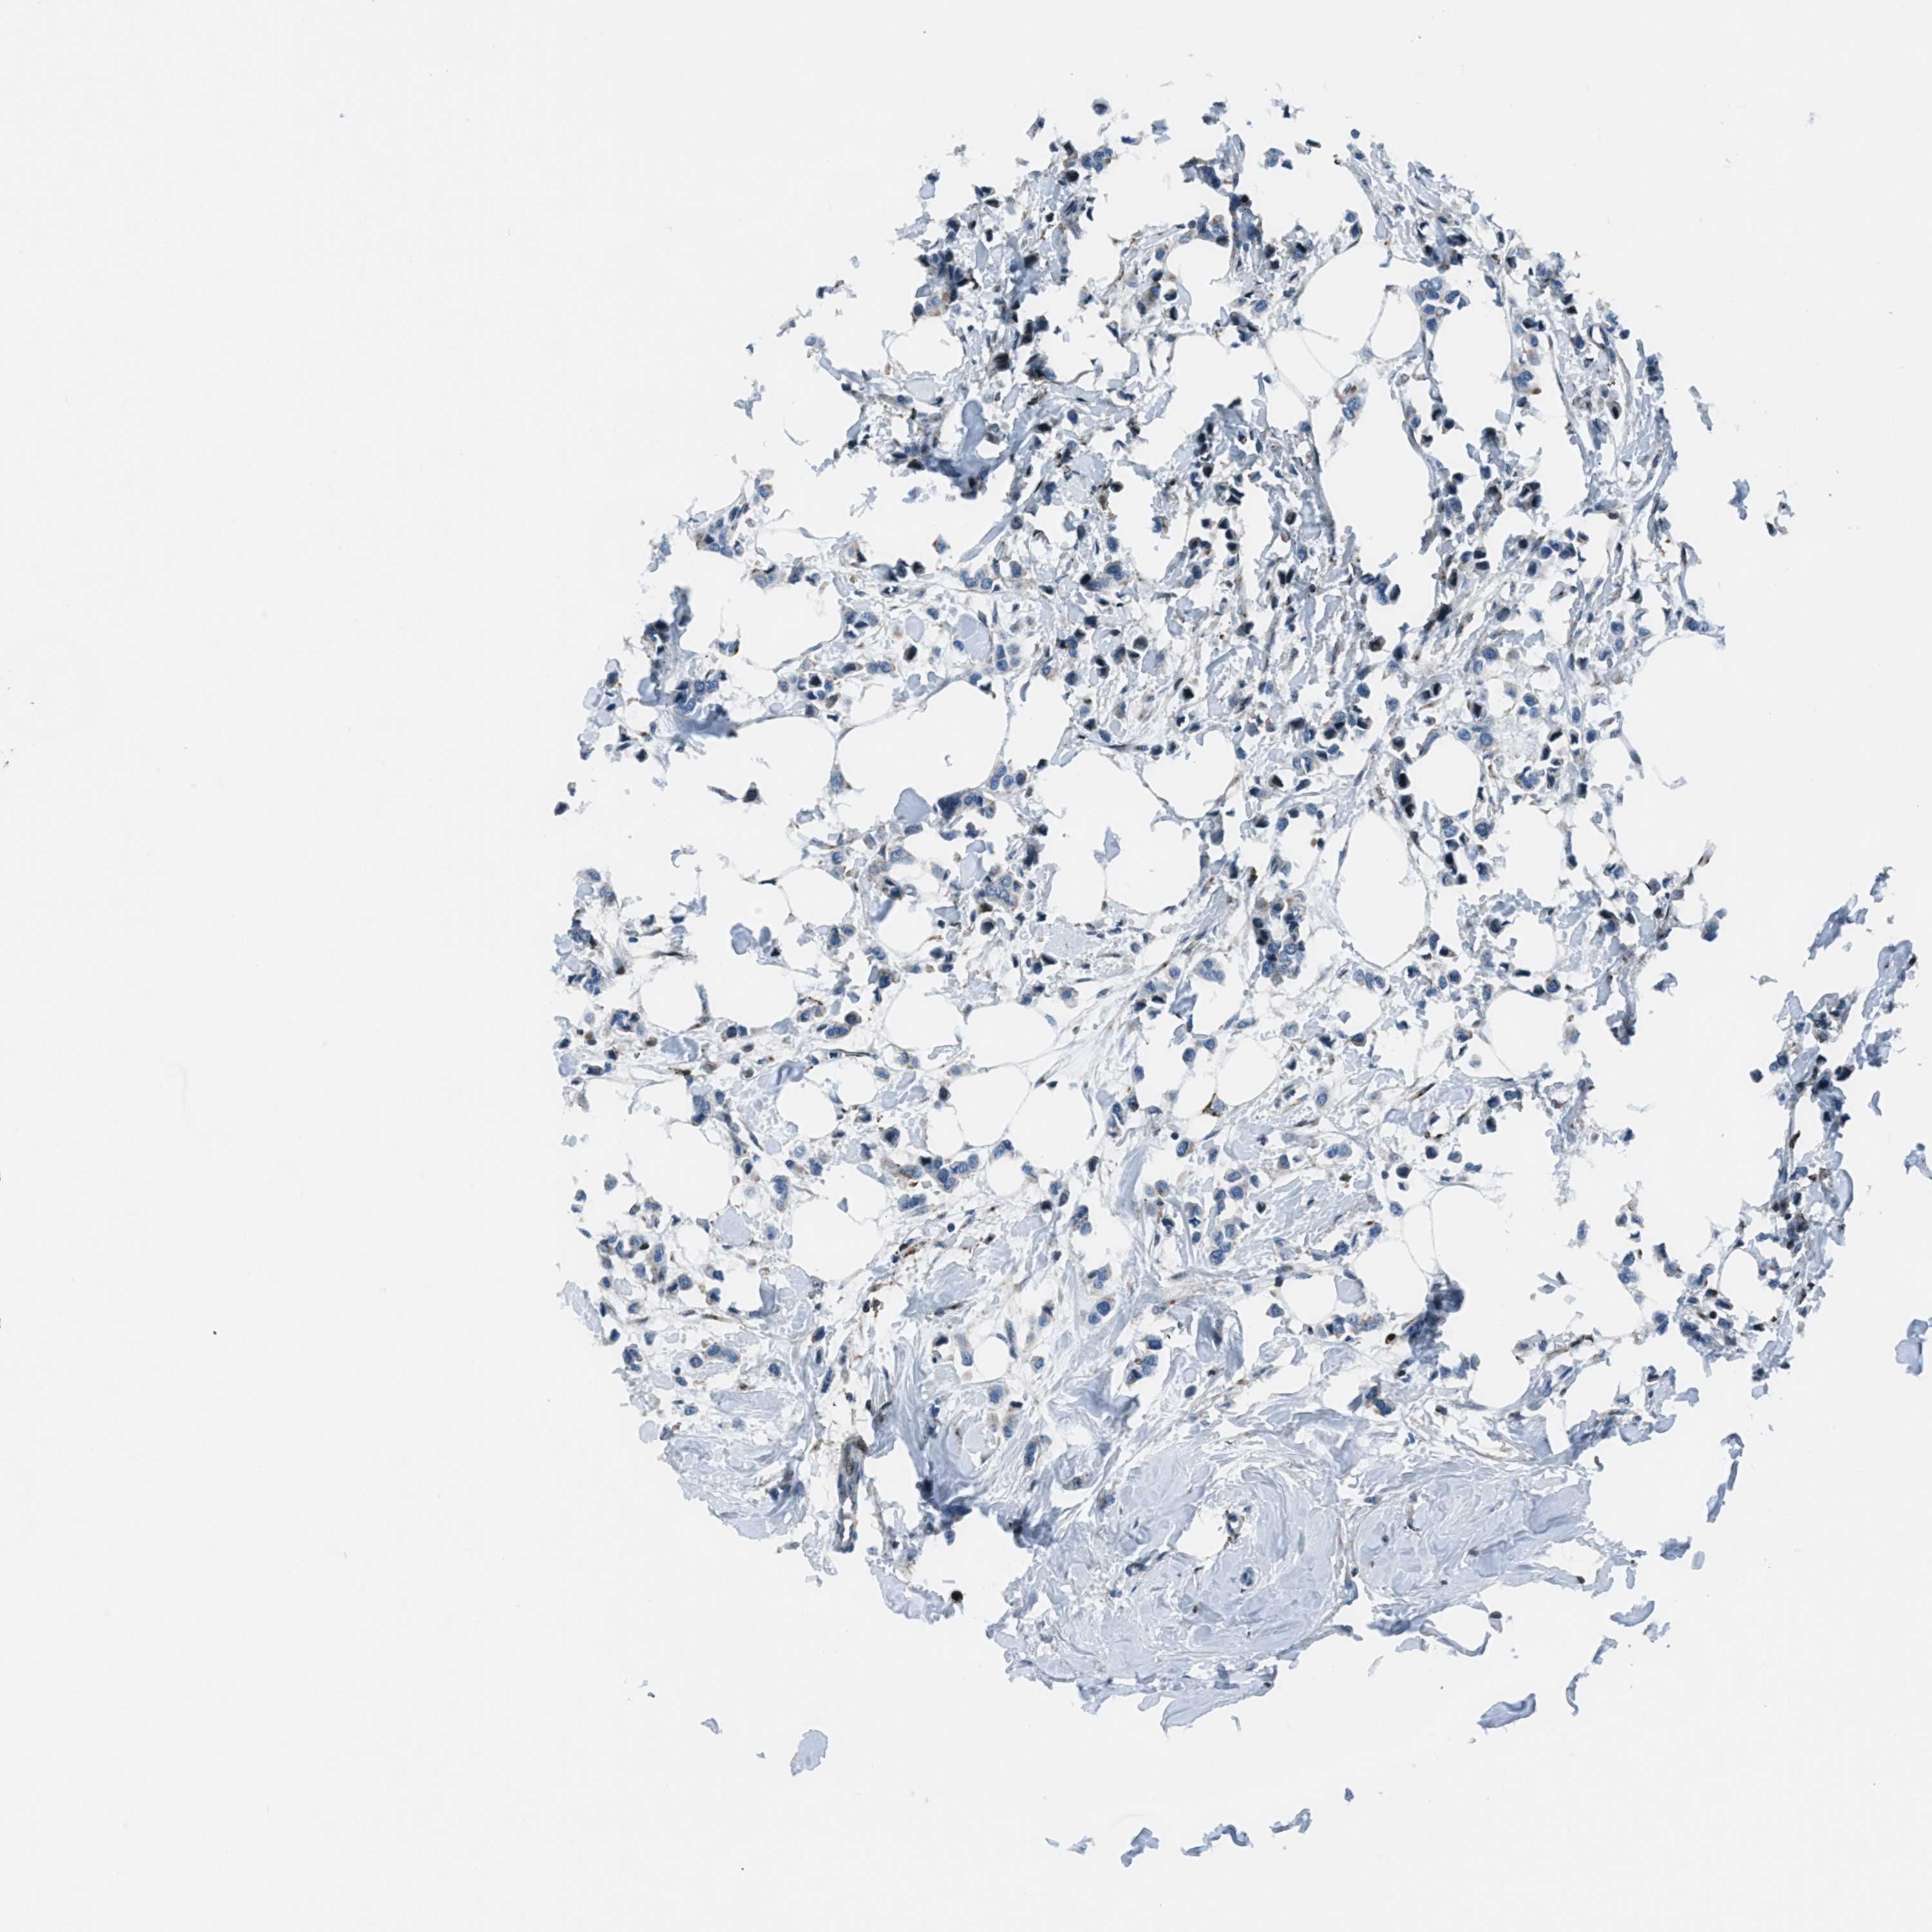

BRCA TCGA BRCA VALIDATION PROTEIN EXPRESSION